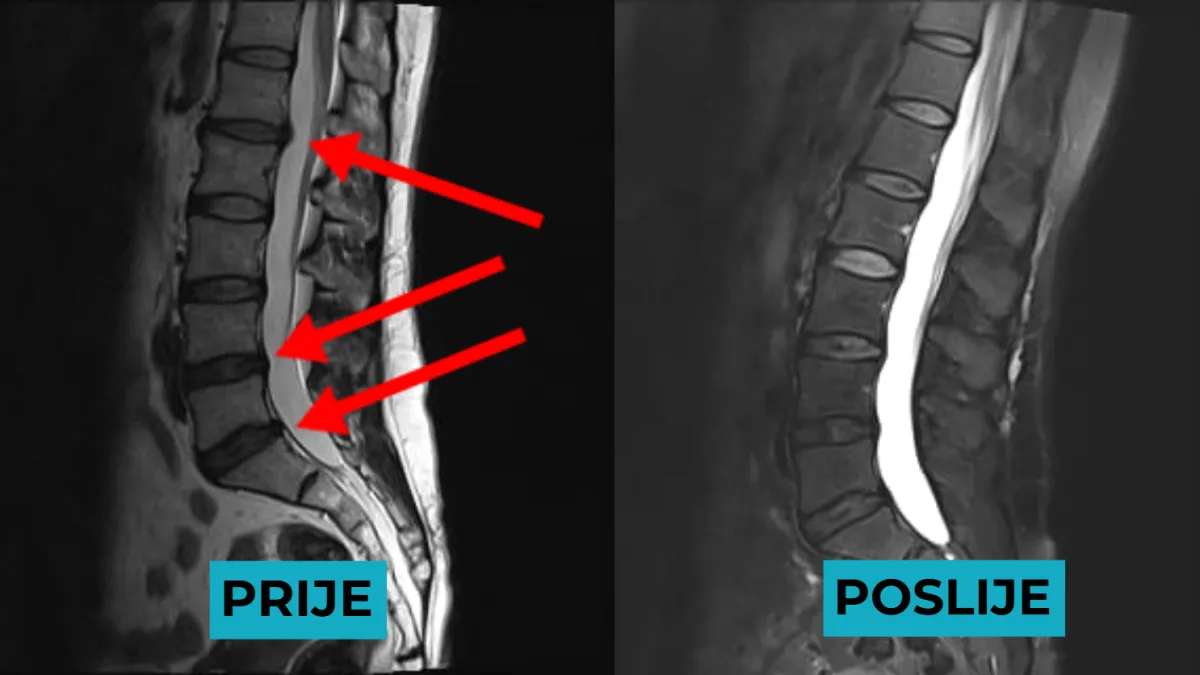

Trajno smanjenje pritiska na diskove i živce

Prirodno cijeljenje i regeneracija diska

Uklanja bol uzrokovanu hernijom diska (protruzija, ekstruzija, bulging), išijasom i degenerativnim promjenama